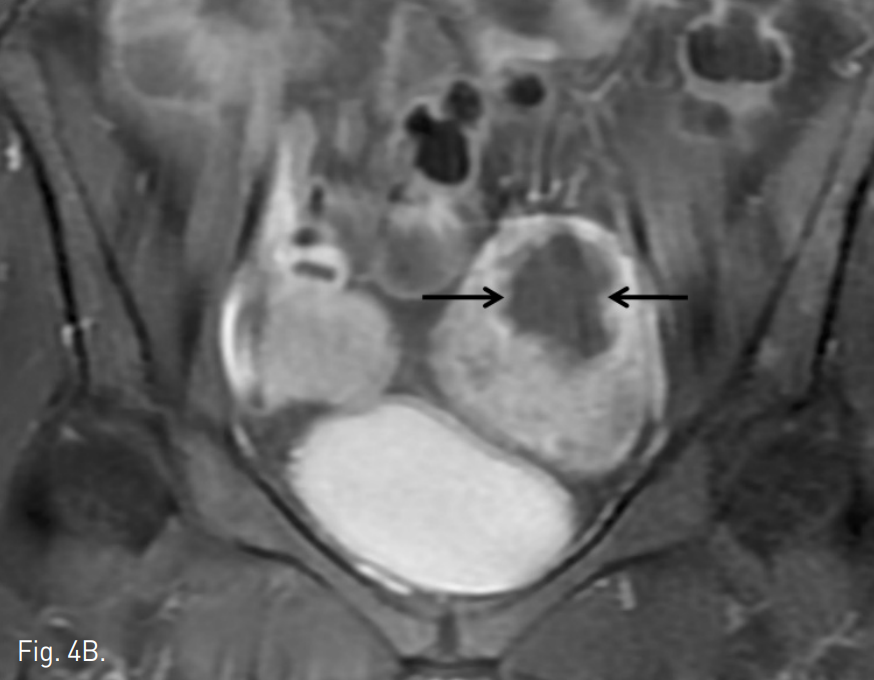

Fig. 4

A, B. T2 weighted (A) and contrast enhanced (B) MR images taken three months after embolization show 44% volume reduction of the left-sided uterus and non-perfusion area in adenomyosis (arrows in A and B).